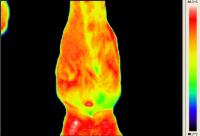

Rasmus - Pferd mit Arthrose - Horse with Osteoarthritis